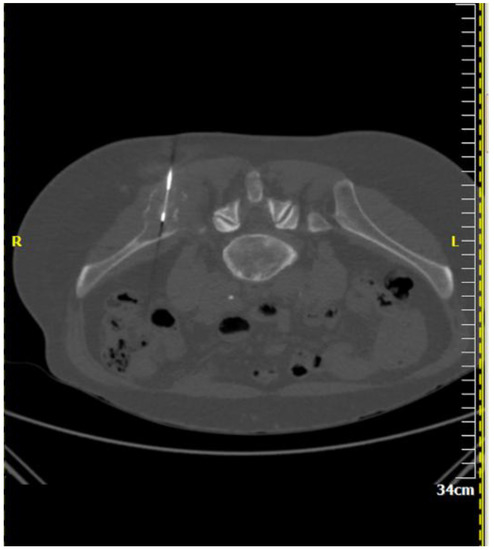

Figure 2.

A 64-year-old male patient with multiple osteolytic lesions. Computed tomography axial scan: there is a lytic lesion in the right iliac bone. The result of percutaneous, imaging-guided biopsy was metastasis from small cell bronchogenic carcinoma.